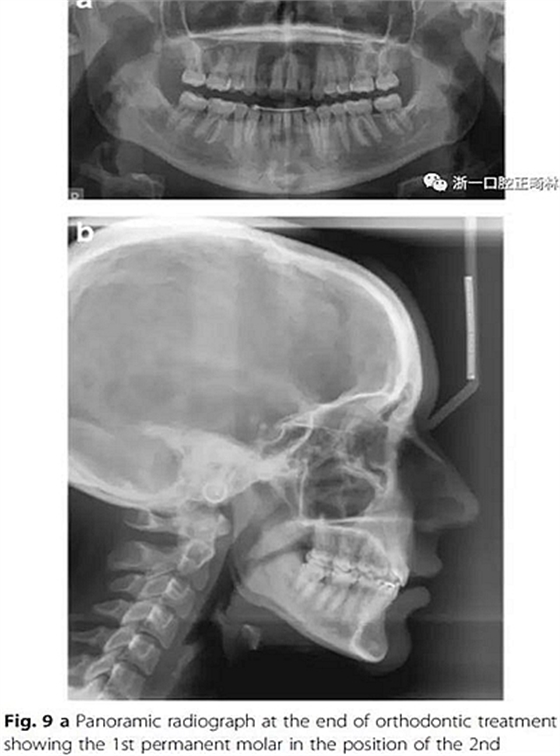

雙側I類尖牙和磨牙關系;完全的間隙關閉(用牙線確定);覆合覆蓋糾正;仍有輕度的中線偏離。頭測分析顯示,下切牙未發(fā)生舌側移動。